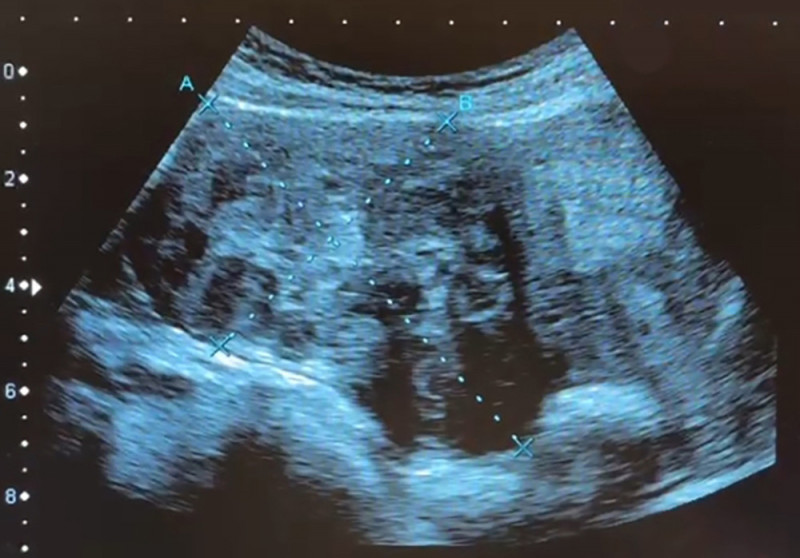

〔記者蔡淑媛/台中報導〕台中一名35歲粉領族即將結婚,擔心罹患多顆子宮肌瘤造成不孕,就醫檢查,發現體內子宮肌瘤又多又大,是年輕型的子宮肌瘤患者,因體質及年紀輕,血中雌激素刺激讓子宮肌瘤快速長大,接受達文西機械手臂手術,由肚臍開刀取出9顆肌 瘤,從1到9公分不等共9顆,最大肌瘤大如拳頭般,但手術沒有明顯傷口,把傷口隱藏在肚臍裡。

謝昌興說,患者的子宮肌瘤不是長在子宮腔內,而是長在子宮璧並往外生長,子宮猶如圓凸形,這類子宮肌瘤在手術摘除後,子宮的功能恢復正常,能自然受孕及生產;如果肌瘤往子宮腔面生長,可能有不孕問題。